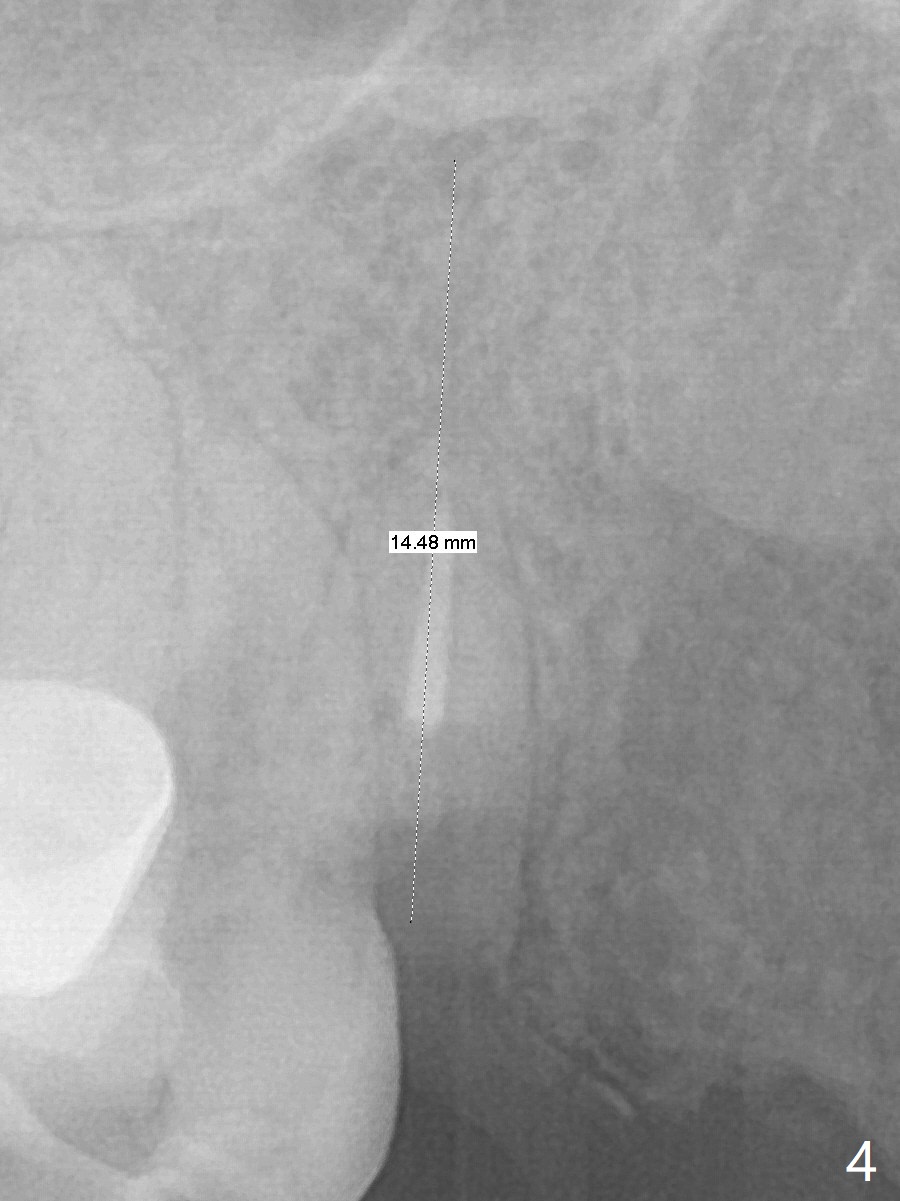

A 38-year-old skinny woman has several missing teeth (Fig.1). Recently a #6-7 cantilever FPD dislodged (Fig.2,3). The buccal plate at #6 must be thin. Socket shield should be indicated, particularly when extraction turns out to be difficult. A 4x13 mm IS implant is going to be inserted as distal as possible to avoid touching the apex of the tooth #5 (Fig.4,5). Since the ridge at #7 is narrow, a 1-piece implant will be placed (possible 2.5x14(2) mm, Fig.5). Take PA after the 1st drills. Take preop photos to show the residual root at #6 and the narrow ridge at #7.